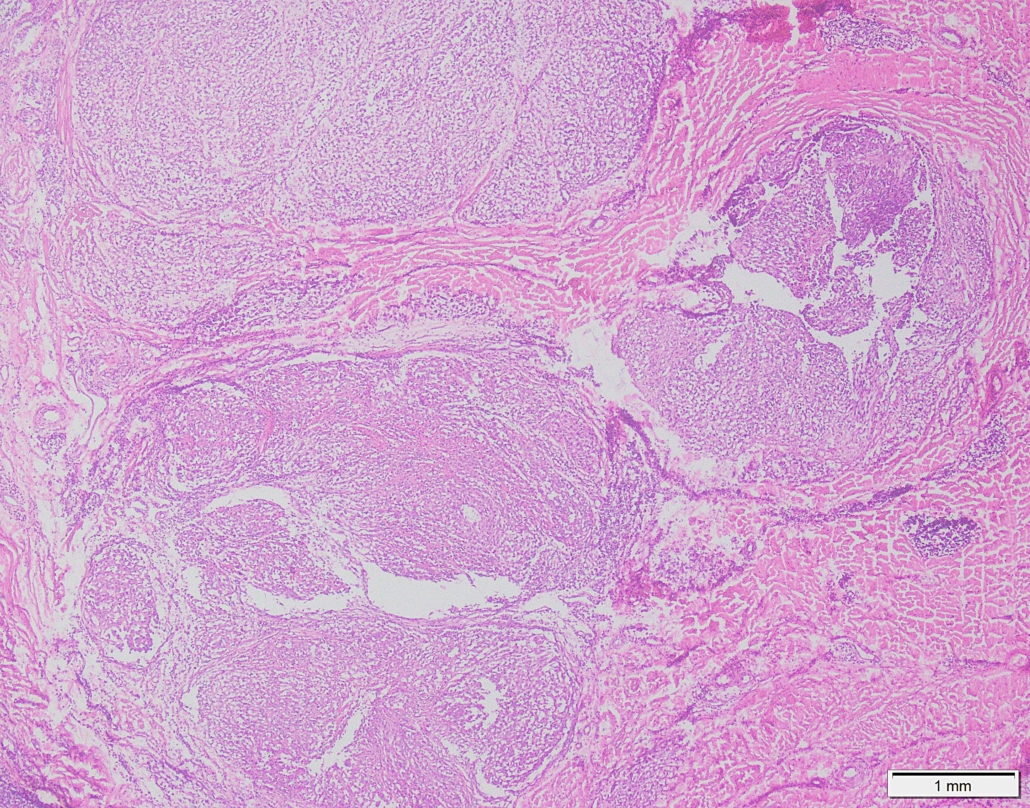

Case 03

Case presented by Dr Shaarif Bashir, FCPS (PAK), Shaukat Khanum Memorial Cancer Hospital and Reserach Centre, Pakistan